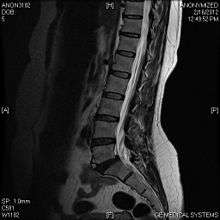

Limbus vertebra

A limbus vertebra also see vertebral epophysis is a bone trauma in the vertebral body bearing a radiographic similarity to a vertebral fracture. The anterior-superior corner of a single vertebra is the common site for this defect although it can also be seen at the inferior corner as well as the posterior or anterior margin. Anatomically, it is assumed to be an intra-vertebral body herniation of the disc material occurring during adolescent growt spurt when the ring apophysis has not yet fused. It was first described by Schmorl in 1927 and later in detail by Leif Sward and Adad baranto.

Viewed in a lateral radiograph, it appears as a triangular shaped bone fragment, not unlike an anterior lip fracture, but with softer edges.

Limbus vertebra is not always symptomatic, but severe cases may lead to more serious pathological conditions and chronic pain. In rare instances, a posterior limbus vertebra has been described causing radiculopathy due to nerve root compression.